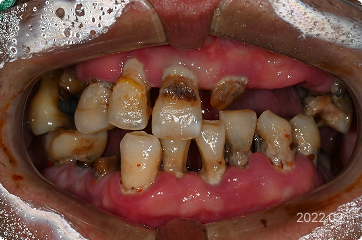

57세, 남 ㅣ전체 임플란트

“치아가 거의 없어서 식사가 어렵고, 일상생활이 제대로 안 돼요.”

치료 전

원데이 임플란트

• 대부분의 치아 상실, 식사 및 생활 불가능

• 하루만에 전체 임플란트 식립

3일만에 전체 즉시 기능 예비치아 장착

• 6개월 후 최종 보철까지 완성